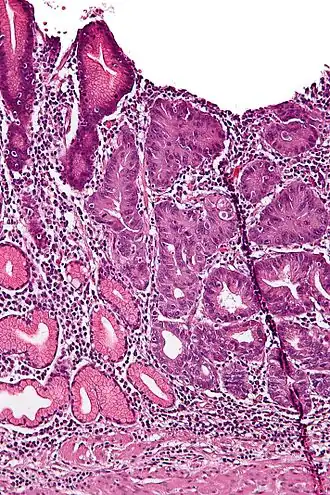

- Epitheeldysplasie van de slijmhuid van de maag- en slokdarm